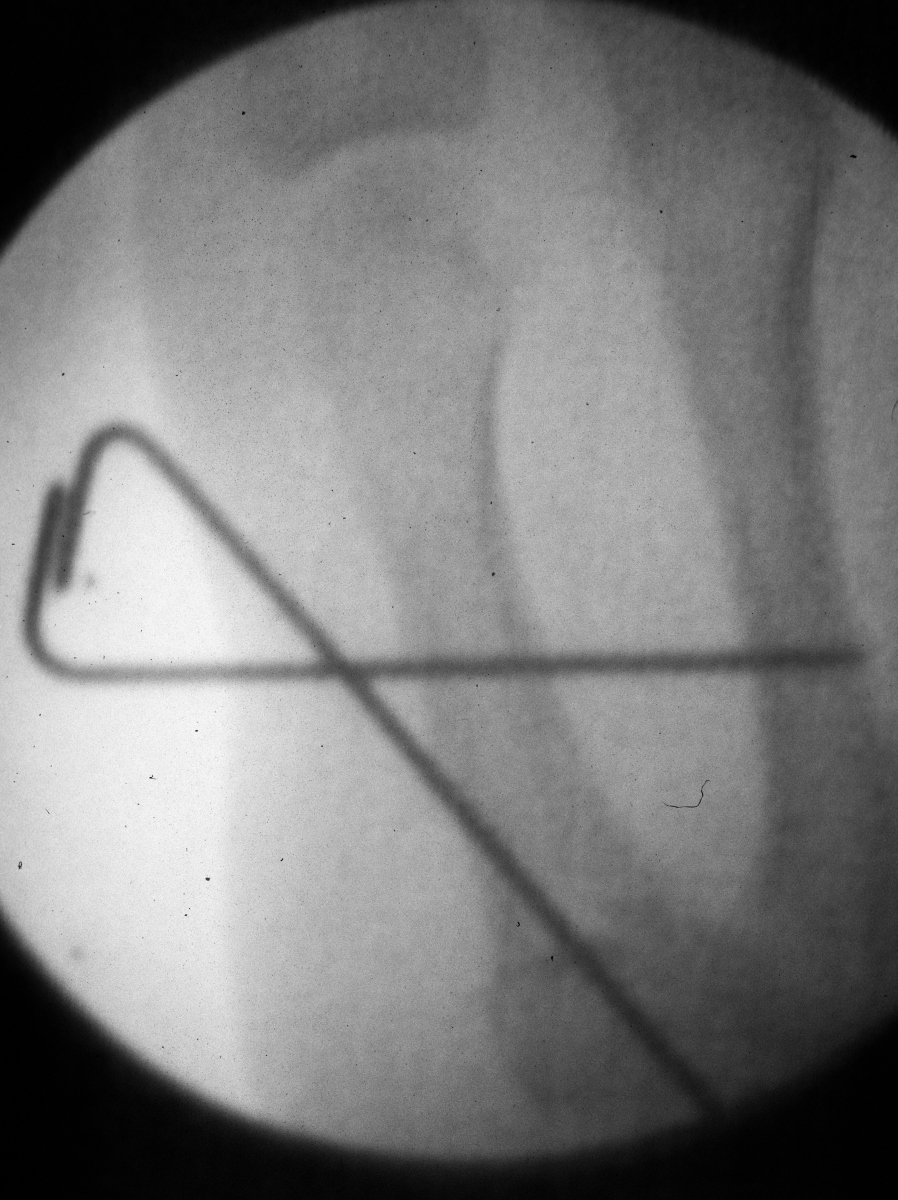

| Pins were left

protruding and bent to overlap. |

| Thermoplastic-pin

construct at 6 weeks, immediately prior to removal. |